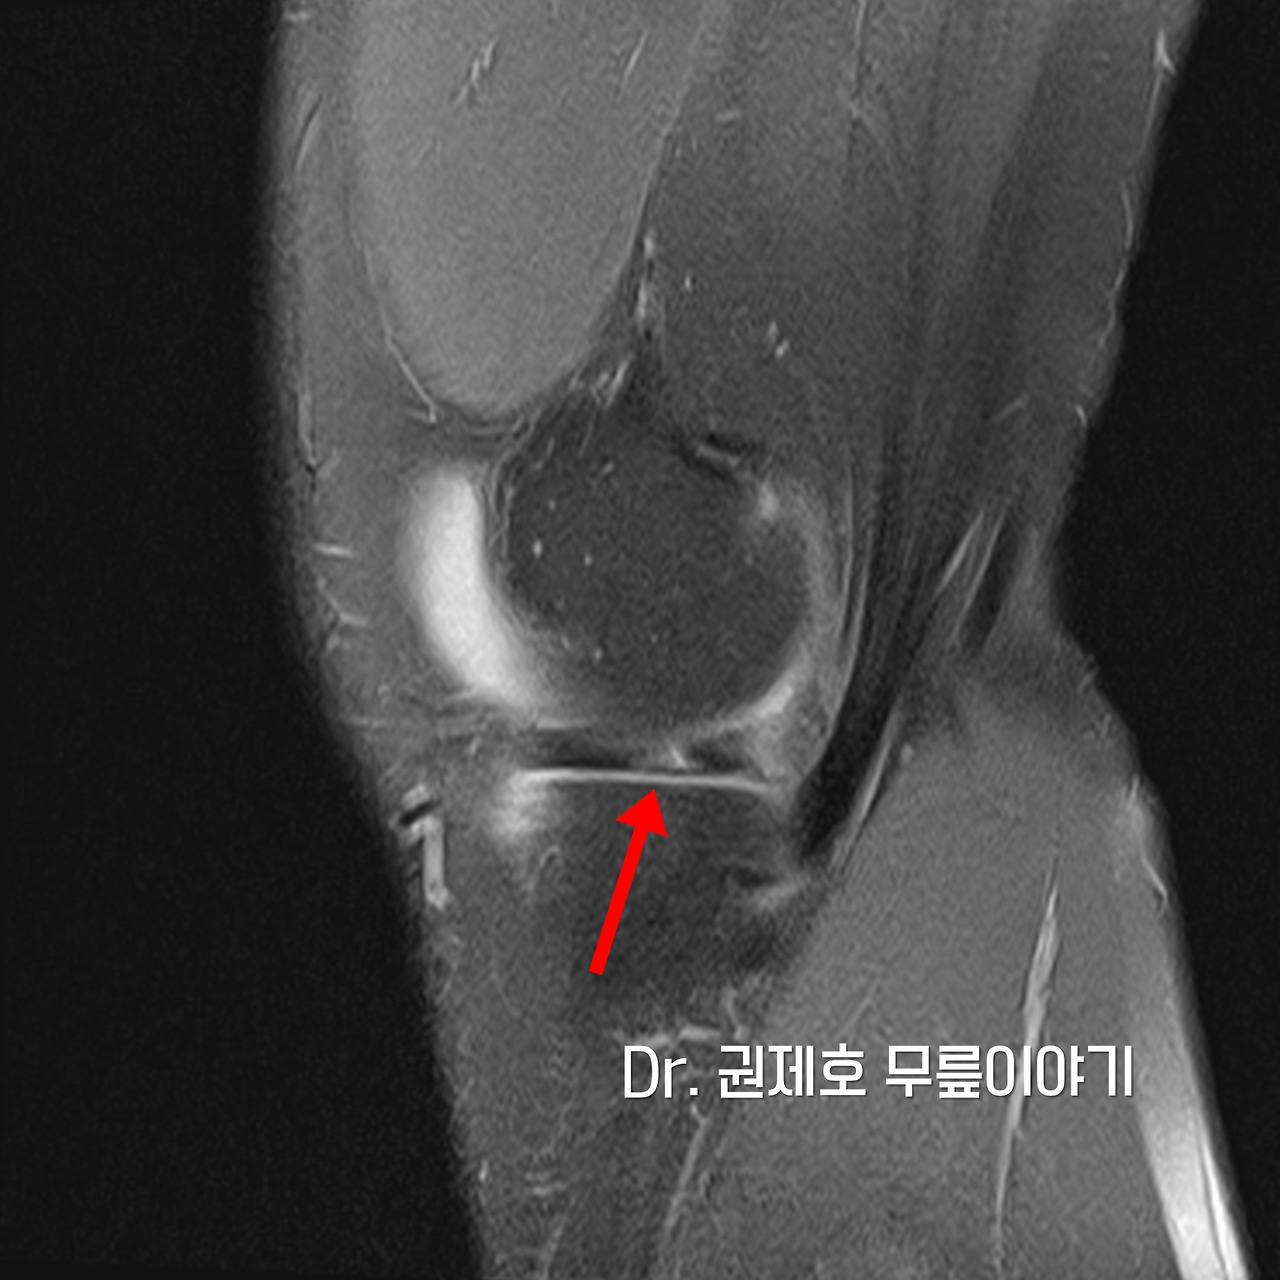

무릎 MRI 검사를 통해 무릎 속에 구조물들 중에서 어떤 것에 문제가 있는지 확인하게 되는데, 검사 결과 무릎연골판이 방사형파열이 있음을 확인하였다.